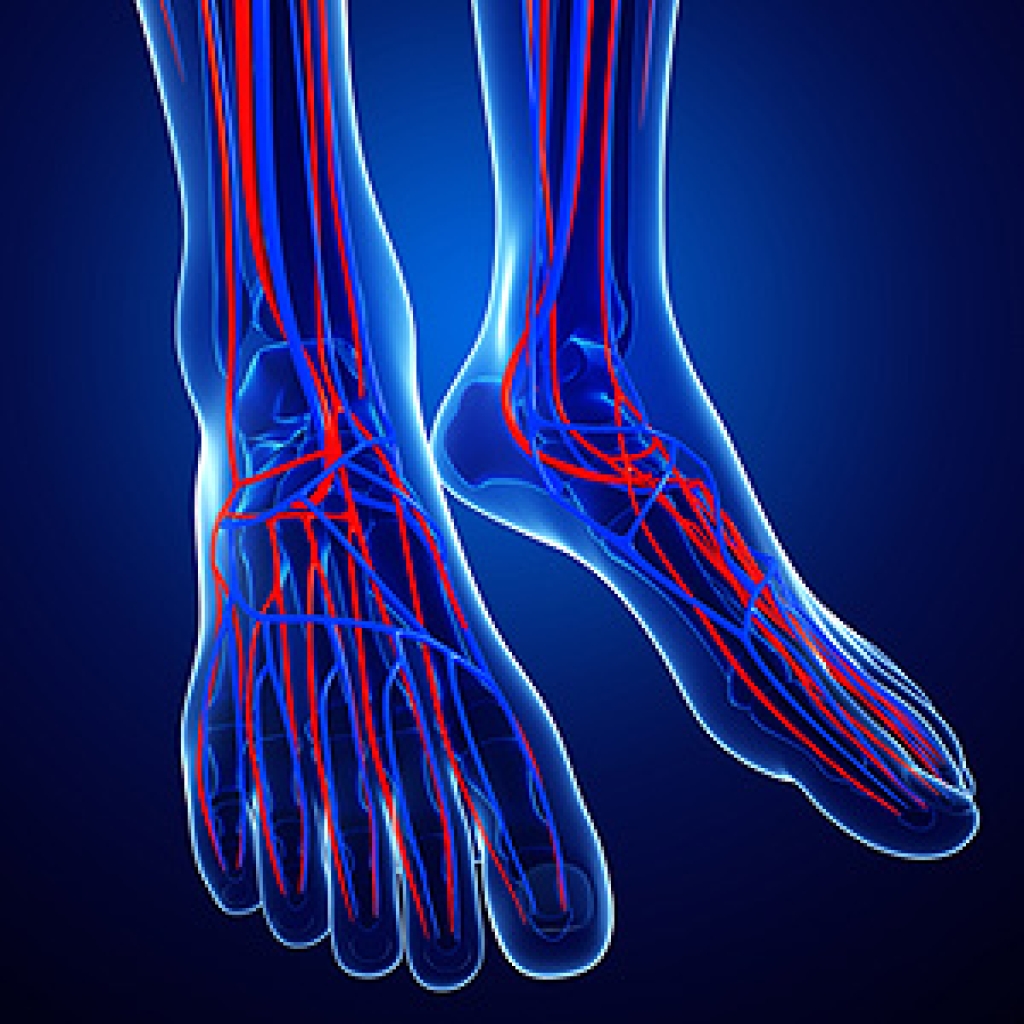

Discoloration of the skin on the feet may be a sign of poor circulation. Problems with circulation can be caused by many different conditions. Raynaud’s disease, a condition that can make the blood vessels in the hands and feet temporarily spasm and constrict, can restrict blood flow and make your feet turn blue, purple, red, or white. Lupus, an autoimmune disease, can cause an inflammation of the blood vessels called vasculitis, which can cause a rash of red or purple dots to appear on the skin. Peripheral artery disease, a condition characterized by poor blood flow to the lower extremities, can cause the feet to gradually turn purple or blue. Diabetes can have a similar effect on the feet. If you notice a discoloration in the skin of your feet, please see that you seek the care of a podiatrist.

Poor blood circulation in the feet and legs is can be caused by peripheral artery disease (PAD), which is the result of a buildup of plaque in the arteries.

Plaque buildup or atherosclerosis results from excess calcium and cholesterol in the bloodstream. This can restrict the amount of blood which can flow through the arteries. Poor blood circulation in the feet and legs are sometimes caused by inflammation in the blood vessels, known as vasculitis.